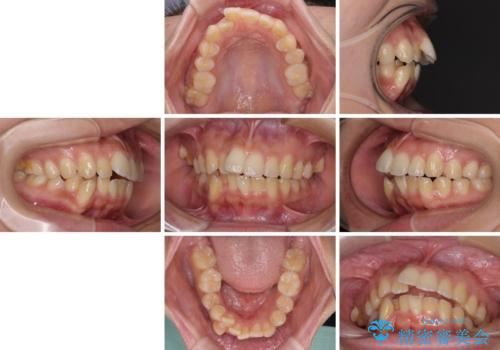

- 八重歯と、上下前歯が接触しないくらい前突した前歯を気にして来院された患者様です。

奥歯の噛み合わせは正常に近い状態でしたが、右上の奥歯に突起があったり、上下前歯が非接触であったりしていたため、補助装置を使用して上顎前歯を積極的に引っ込めるように計画しました。

口元の突出感を改善するために上下左右の小臼歯4本を抜歯し、ワイヤー装置によりデコボコを解消しながら口元の突出感も改善していくこととしました。